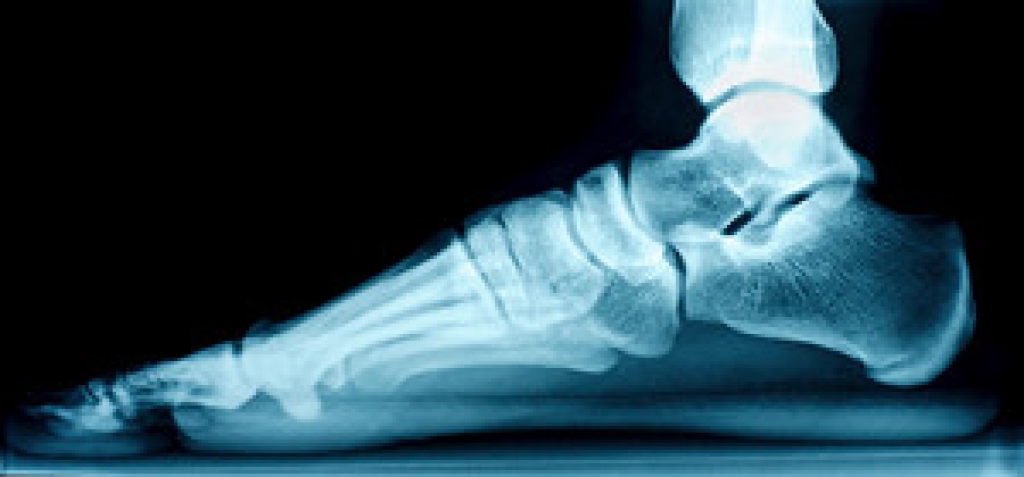

The Achilles tendon is a tendon that connects the lower leg muscles and calf to the heel of the foot. It is the strongest tendon in the human body and is essential for making movement possible. Because this tendon is such an integral part of the body, any injuries to it can create immense difficulties and should immediately be presented to a doctor.